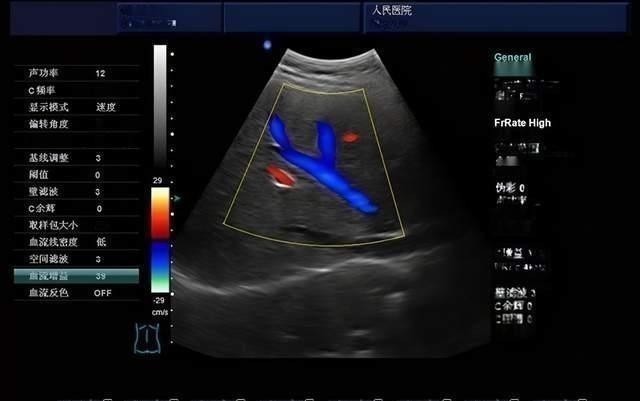

多普勒彩超一般的B超都是二维平面,三维B超可以在多个角度的回波信号处理成立体图像,这个原理就像激光扫描3D成像一样。